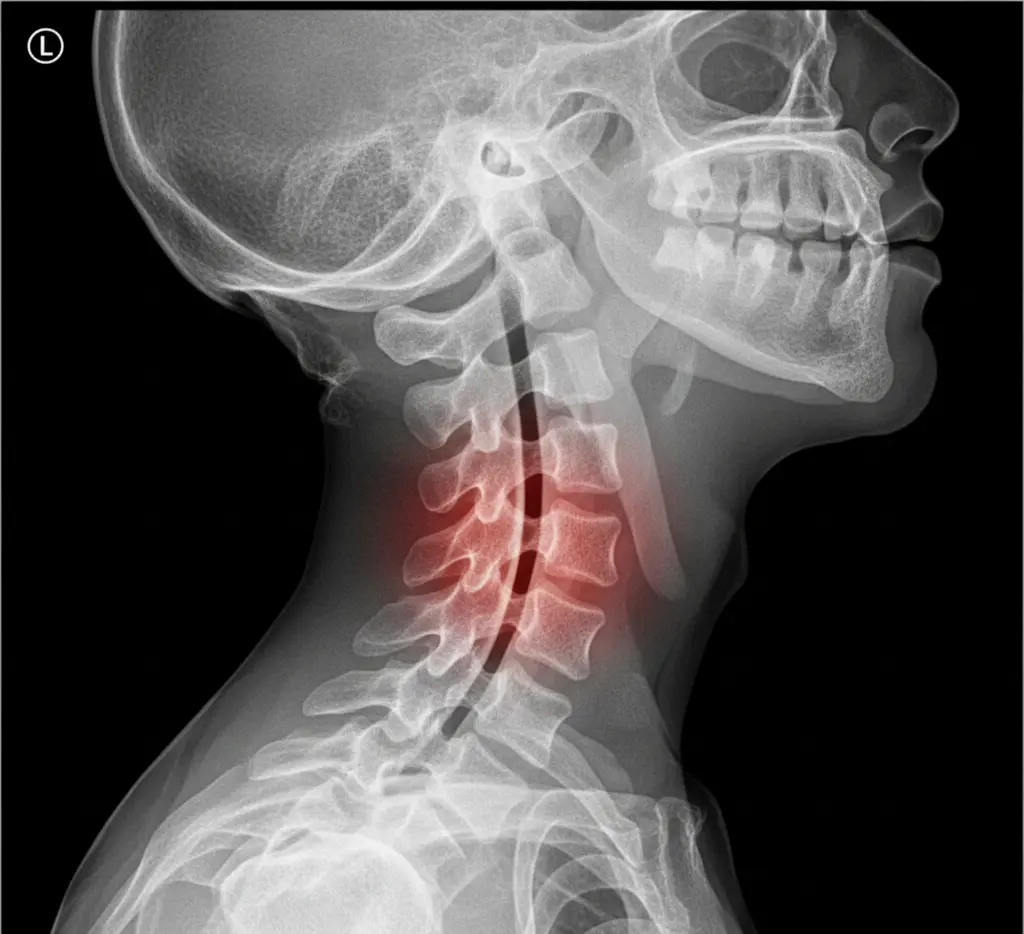

Cervical spinal stenosis is a condition where the spinal canal in the neck narrows, potentially compressing the spinal cord and nerve roots. This narrowing can occur in the cervical spine’s bony openings (foramina), reducing space for nerves and/or the spinal cord.

Cervical Spine Stenosis

In the cervical spine, narrowing can cause different symptoms based on whether the spinal cord or nerve roots are compressed: